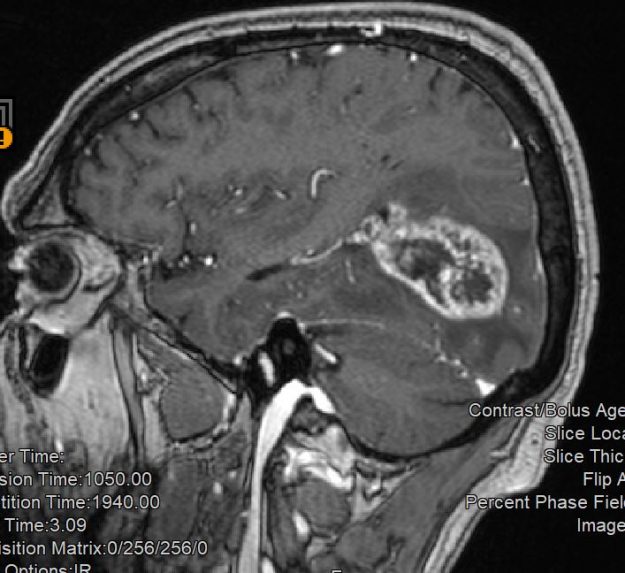

Ασθενής γυναίκα 58 ετών με πονοκεφάλους και διαταραχές όρασης. Ο οφθαλμολογικός έλεγχος έδειξε οίδημα οπτικών θηλών άμφω και σημαντικό περιορισμό των οπτικών πεδίων. Τα συμπτώματα της ασθενούς ήταν προοδευτικά επιδεινούμενα, το ίδιο και οι εξετάσεις της. Η μαγνητική εγκεφάλου ανέδειξε ευμεγέθη αραχνοειδή κύστη δεξιά κροταφικά με σημαντική πίεση επί του υγιούς εγκεφάλου και παρεκτόπιση των…